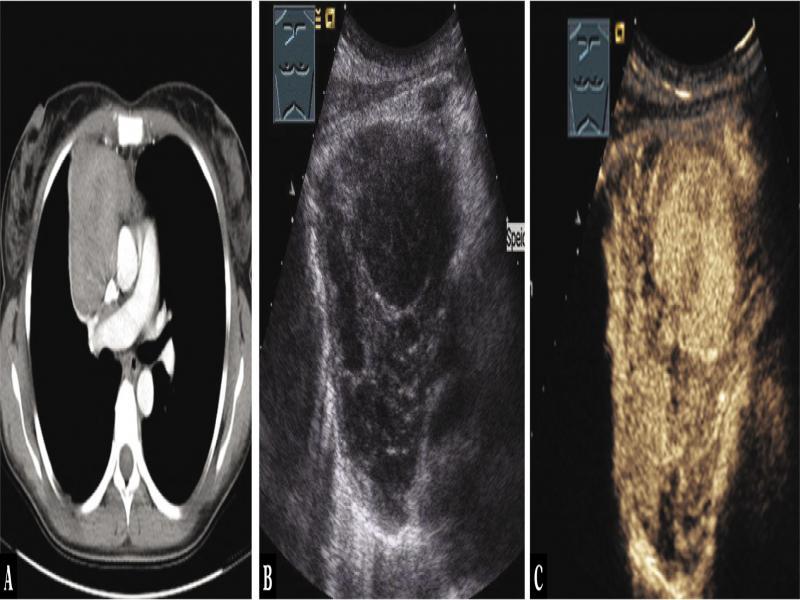

Fig. 1.

A 40-year-old female patient with mediastinal tumor in the anterior mediastinum as an incidental finding in computed tomography (A). Thoracic ultrasound indicated anechoic nodes (B), which showed no enhancement on contrast-enhanced ultrasound (C). Mediastinoscopy was performed, and regressive thymoma was histologically confirmed